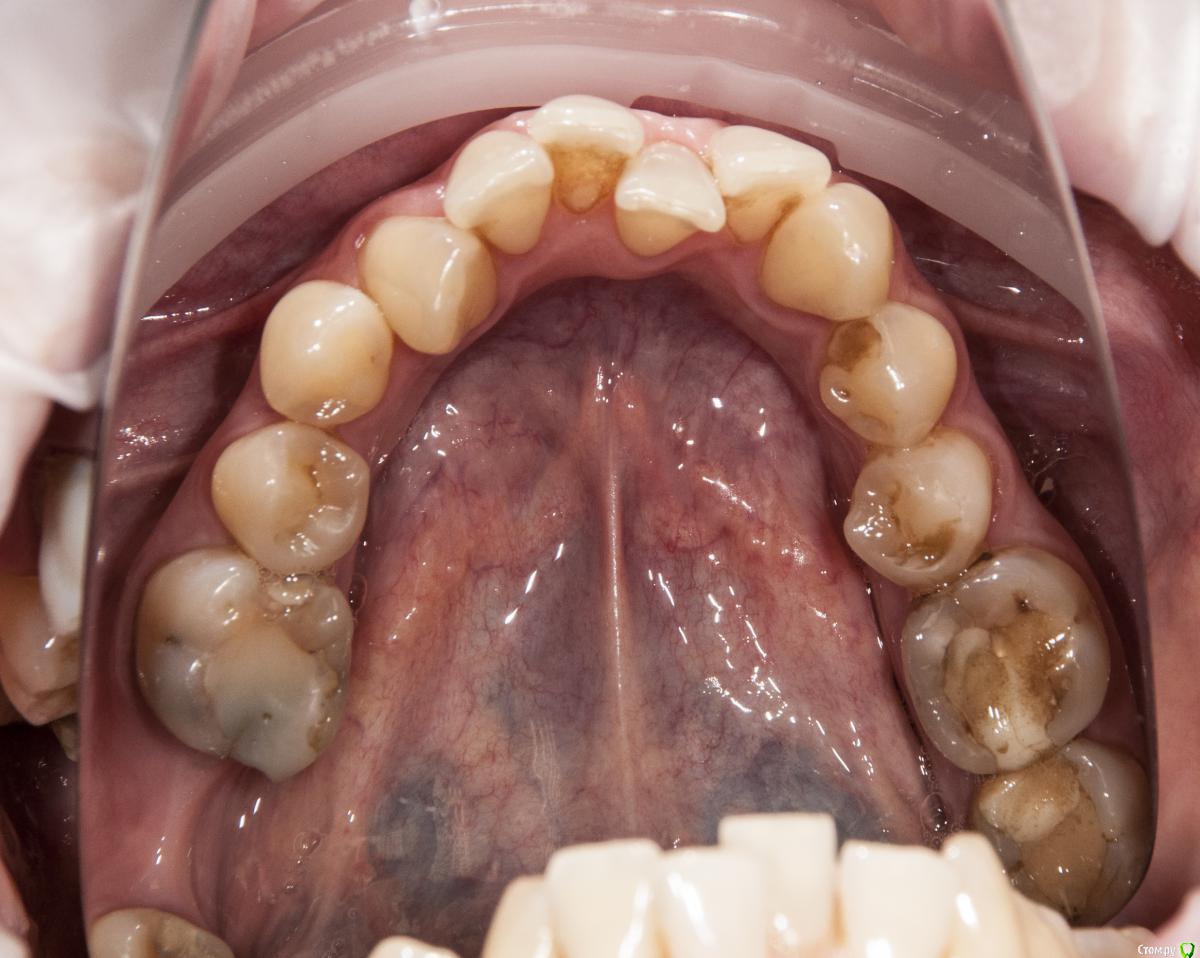

kamranchick Опубликовано 4 мая, 2018 Поделиться Опубликовано 4 мая, 2018 Добрый день Уважаемые коллеги, имеются проблемы с ортодонтией в нашем славном городе.Какие будут предложения по кейсу, сколько визитов и по ценникам, можно в личку.Пациент готов ездить в другие городаP.S пациент тоже будет следить за ходом этой ветки))) Ссылка на комментарий

krokomot Опубликовано 4 мая, 2018 Поделиться Опубликовано 4 мая, 2018 А импланты уже успели установить. 1 Ссылка на комментарий

kamranchick Опубликовано 4 мая, 2018 Автор Поделиться Опубликовано 4 мая, 2018 А импланты уже успели установить.Как видите вопросов много конечно, но что можно предложить имея такую картину. Ссылка на комментарий

krokomot Опубликовано 4 мая, 2018 Поделиться Опубликовано 4 мая, 2018 в данной ситуации конечно шляпа у пациента, если совсем все плохо, можно бы, ло бы просанировать для начала, снять скан, затем, поробовать на инвизилайнерах решить основные проблемы в окклюзии , затем тотальное протезирование. Идейка конечно не айс, но всё же выход. Ссылка на комментарий